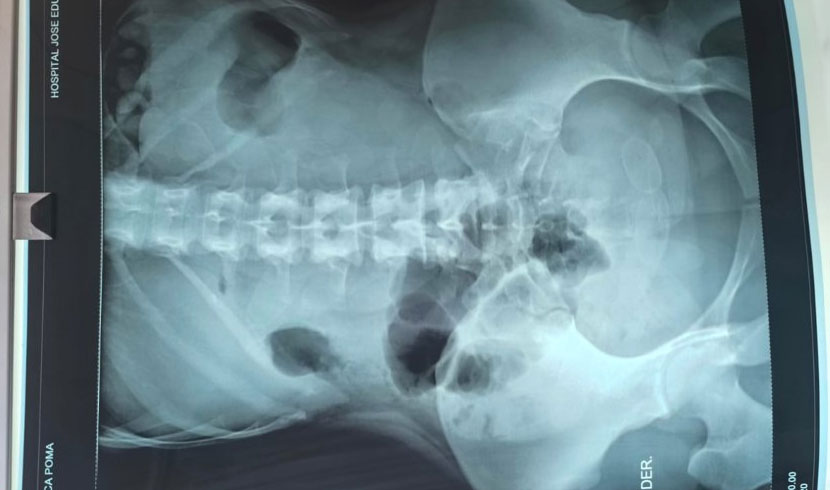

Se realizaron los estudios respectivos y se evidenció que llevaba en su organismo cápsulas, las cuales llevaban en su interior sustancias controladas.